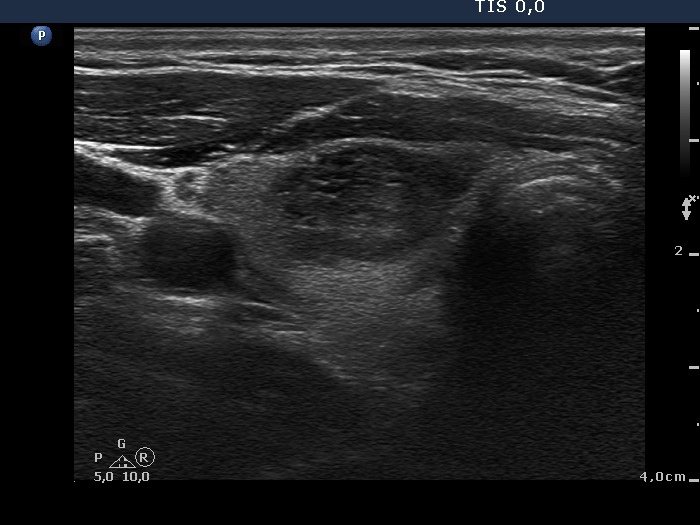

First examination (first and second rows of images)

Ultrasonography. The thyroid was echonormal. There were two moderately hypoechogenic nodules in the ventromedial part of the right lobe. One of them presented irregular borders, hyperechogenic granules and cystic degeneration. The left thyroid contained several nodules with different echo structures.

Cytology was performed from the nodule in the right lobe and resulted in benign, follicular proliferation..